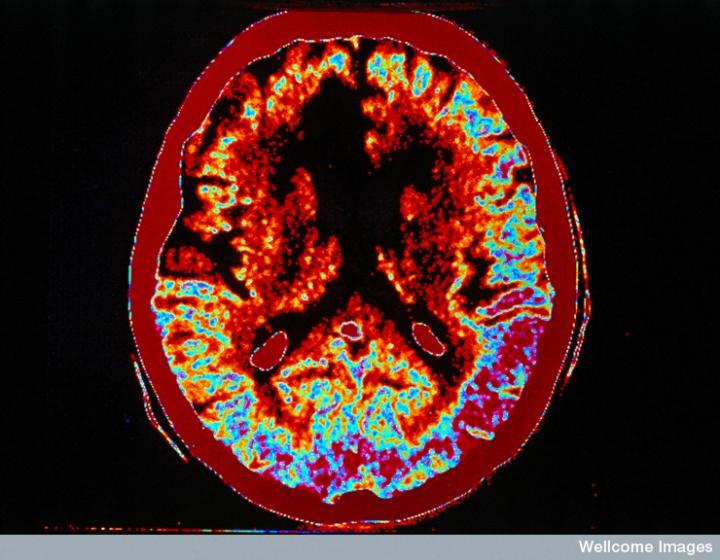

左侧的血流图比右侧的X射线CT扫描显示出更多的中风损伤

慢性中风患者的脑成像

CT扫描的主图显示左侧有一些中风损伤,由 Wellcome Images提供。Wellcome Photo Library提供的慢性中风的附加图像 ,Wellcome Images,QL 从胚胎干细胞培养的神经元。Ying & A. Smith, Wellcome Images 和 Yirui Sun, Wellcome Images 移植的小鼠神经干细胞。